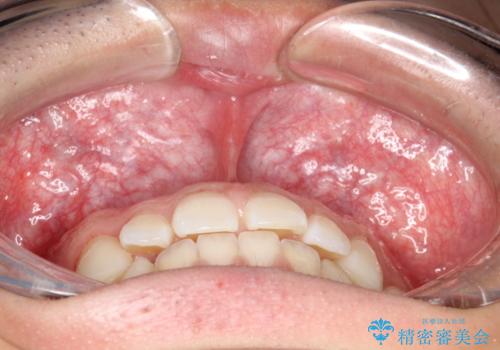

前歯の隙間がきになる インビザラインですきっ歯の治療

- 上の前歯の隙間を主訴に来院されました。

正中に隙間があり、かみ合わせが深い過蓋咬合という状態でした。

インビザラインにて矯正治療を行いました。